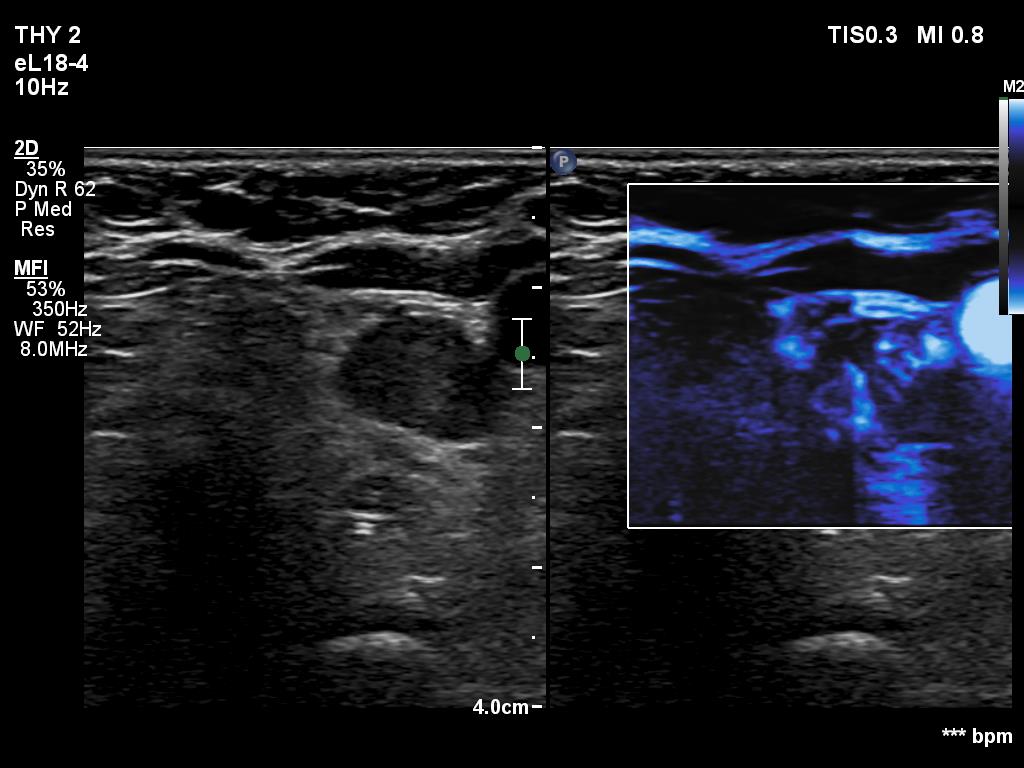

Right lobe, longitudinal scan

Under the left lobe, transverse scan, microflow imaging. There is a vessel entering the mass at its dorsal part.